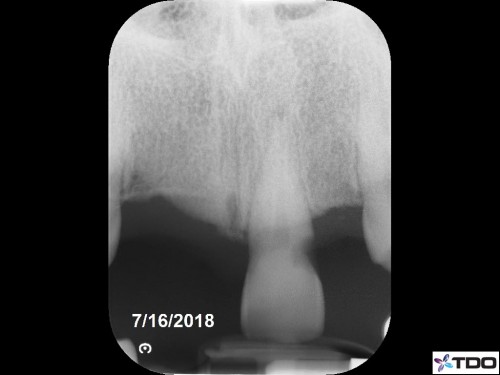

47 yof. Symptomatic partially necrotic pulp. First visit instrumented with #15K to length. Second visit apically gauged to a size 40.